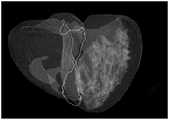

FIG. 8 is a graph of results of an alternative cardiac coronary vessel naming according to an embodiment of the present application;

In an alternative embodiment, as shown in fig. 8, fig. 8 is a diagram of the result of naming the coronary vessels in the heart, the cross plane is perpendicular to fig. 8, because of the mirror image relationship of the diagram, the right crown is the left half of the diagram, the main PL can be judged according to the cross plane, the central line of the right crown which passes through the cross plane and extends furthest backwards is the main PL, the central line except the main PL and the bifurcation point of the main PL are calculated, the part from the bifurcation point of the processed central line to the end point is calculated, and the intersection line with the interventricular sulcus scores are the smallest PD, and two bifurcation points, namely PD1 and PD2, can be seen in fig. 8, wherein the scoring rules are as follows: the product of the average value of the minimum distances from each point on the central line behind the bifurcation point to the interchamber groove intersecting line and the minimum value of the distances from all points on the central line to the interchamber groove intersecting line, namely the product of the average value and the minimum value is minimum.